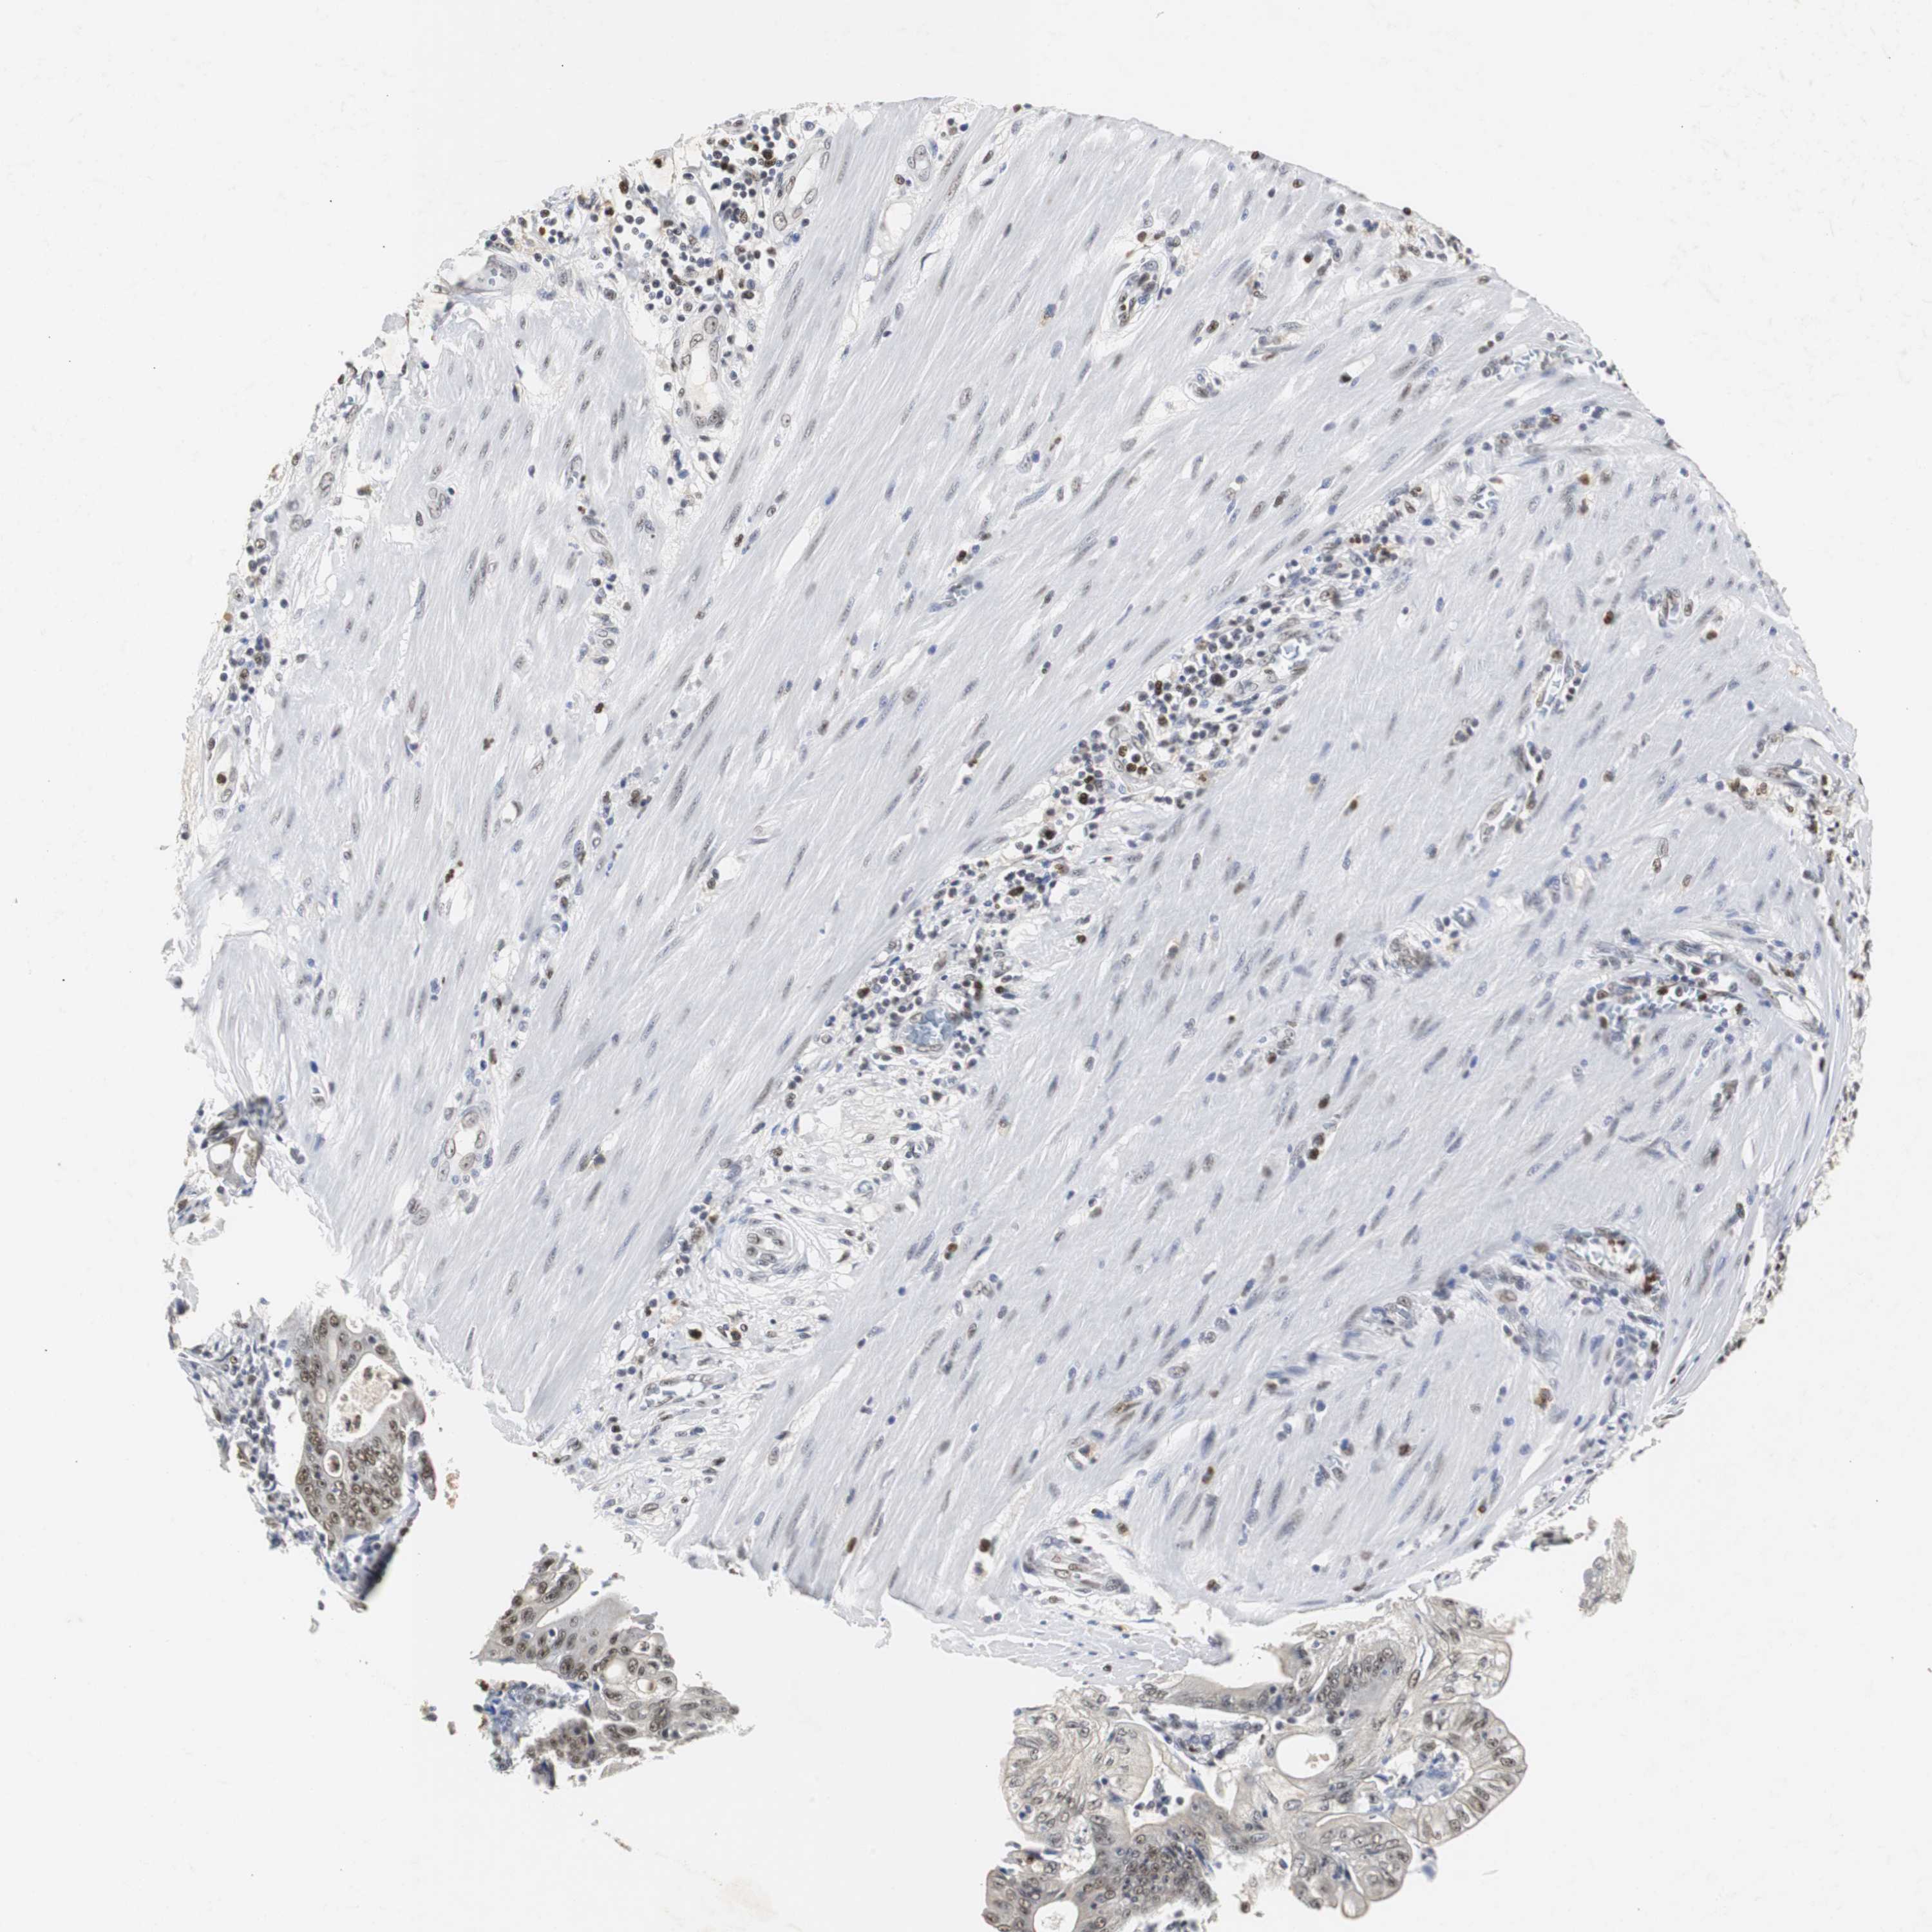

PANCREATIC CANCER - Protein expressioni

A mouse-over function shows sample information and annotation data. Click on an image to view it in a full screen mode. Samples can be filtered based on level of antibody staining by selecting one or several of the following categories: high, medium, low and not detected. The assay and annotation is described here.

Note that samples used for immunohistochemistry by the Human Protein Atlas do not correspond to samples in the TCGA dataset.

Antibody stainingi

Antibody staining in the annotated cell types in the current human tissue is reported as not detected, low, medium, or high, based on conventional immunohistochemistry profiling in selected tissues. This score is based on the combination of the staining intensity and fraction of stained cells.

Each image is clickable and will lead to virtual microscopy that enables deeper exploration of all samples and also displays staining intensity scores, fraction scores and subcellular localization as well as patient and tissue information for each sample.

Antibody HPA007072

Antibody HPA007151

Staining

High

Medium

Low

Not detected

Intensity

Strong

Moderate

Weak

Negative

Quantity

>75%

75%-25%

<25%

None

Location

Nuclear

Cytoplasmic/membranous

Cytoplasmic/membranous,nuclear

Adenocarcinoma, NOS

Adenocarcinoma, metastatic, NOS